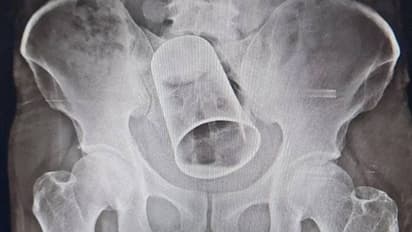

എന്നാല് എക്സറേ പരിശോധനയില് യുവാവിന്റെ ശരീരത്തിനുള്ളില് സ്റ്റീല് ഗ്ലാസ് കുടുങ്ങികിടക്കുന്നത് ഡോക്ടര്മാര് കണ്ടെത്തി. ഇതോടെയാണ് കൃഷ്ണയുടെ സുഹൃത്തുക്കള് ചെയ്ത കൊടും. ക്രൂരത പുറത്തായത്. യുവാവിനെ ചികിത്സിച്ച ഡോക്ടര്മാര് മലദ്വാരത്തിലൂടെ ഗ്ലാസ് പുറത്തെടുക്കാന് ശ്രമിച്ചെങ്കിലും ഫലംകണ്ടില്ല. പിന്നീട് യുവാവിനെ ശസ്ത്രക്രിയയ്ക്ക് വിധേയനാക്കുരയായിരുന്നു. ആശുപത്രിയിലെ ശസ്ത്രക്രിയ വിഭാഗം മേധാവി പ്രൊഫ. ഡോ. ചരണ് പാണ്ഡയുടെ നേതൃത്വത്തിലാണ് ശസ്ത്രക്രിയ നടത്തിയത്. യുവാവ് സുഖംപ്രാപിക്കുന്നുവെന്ന് ഡോ. ചരണ് പാണ്ഡെ ദേശീയ മാധ്യമത്തോട് പ്രതികരിച്ചു.